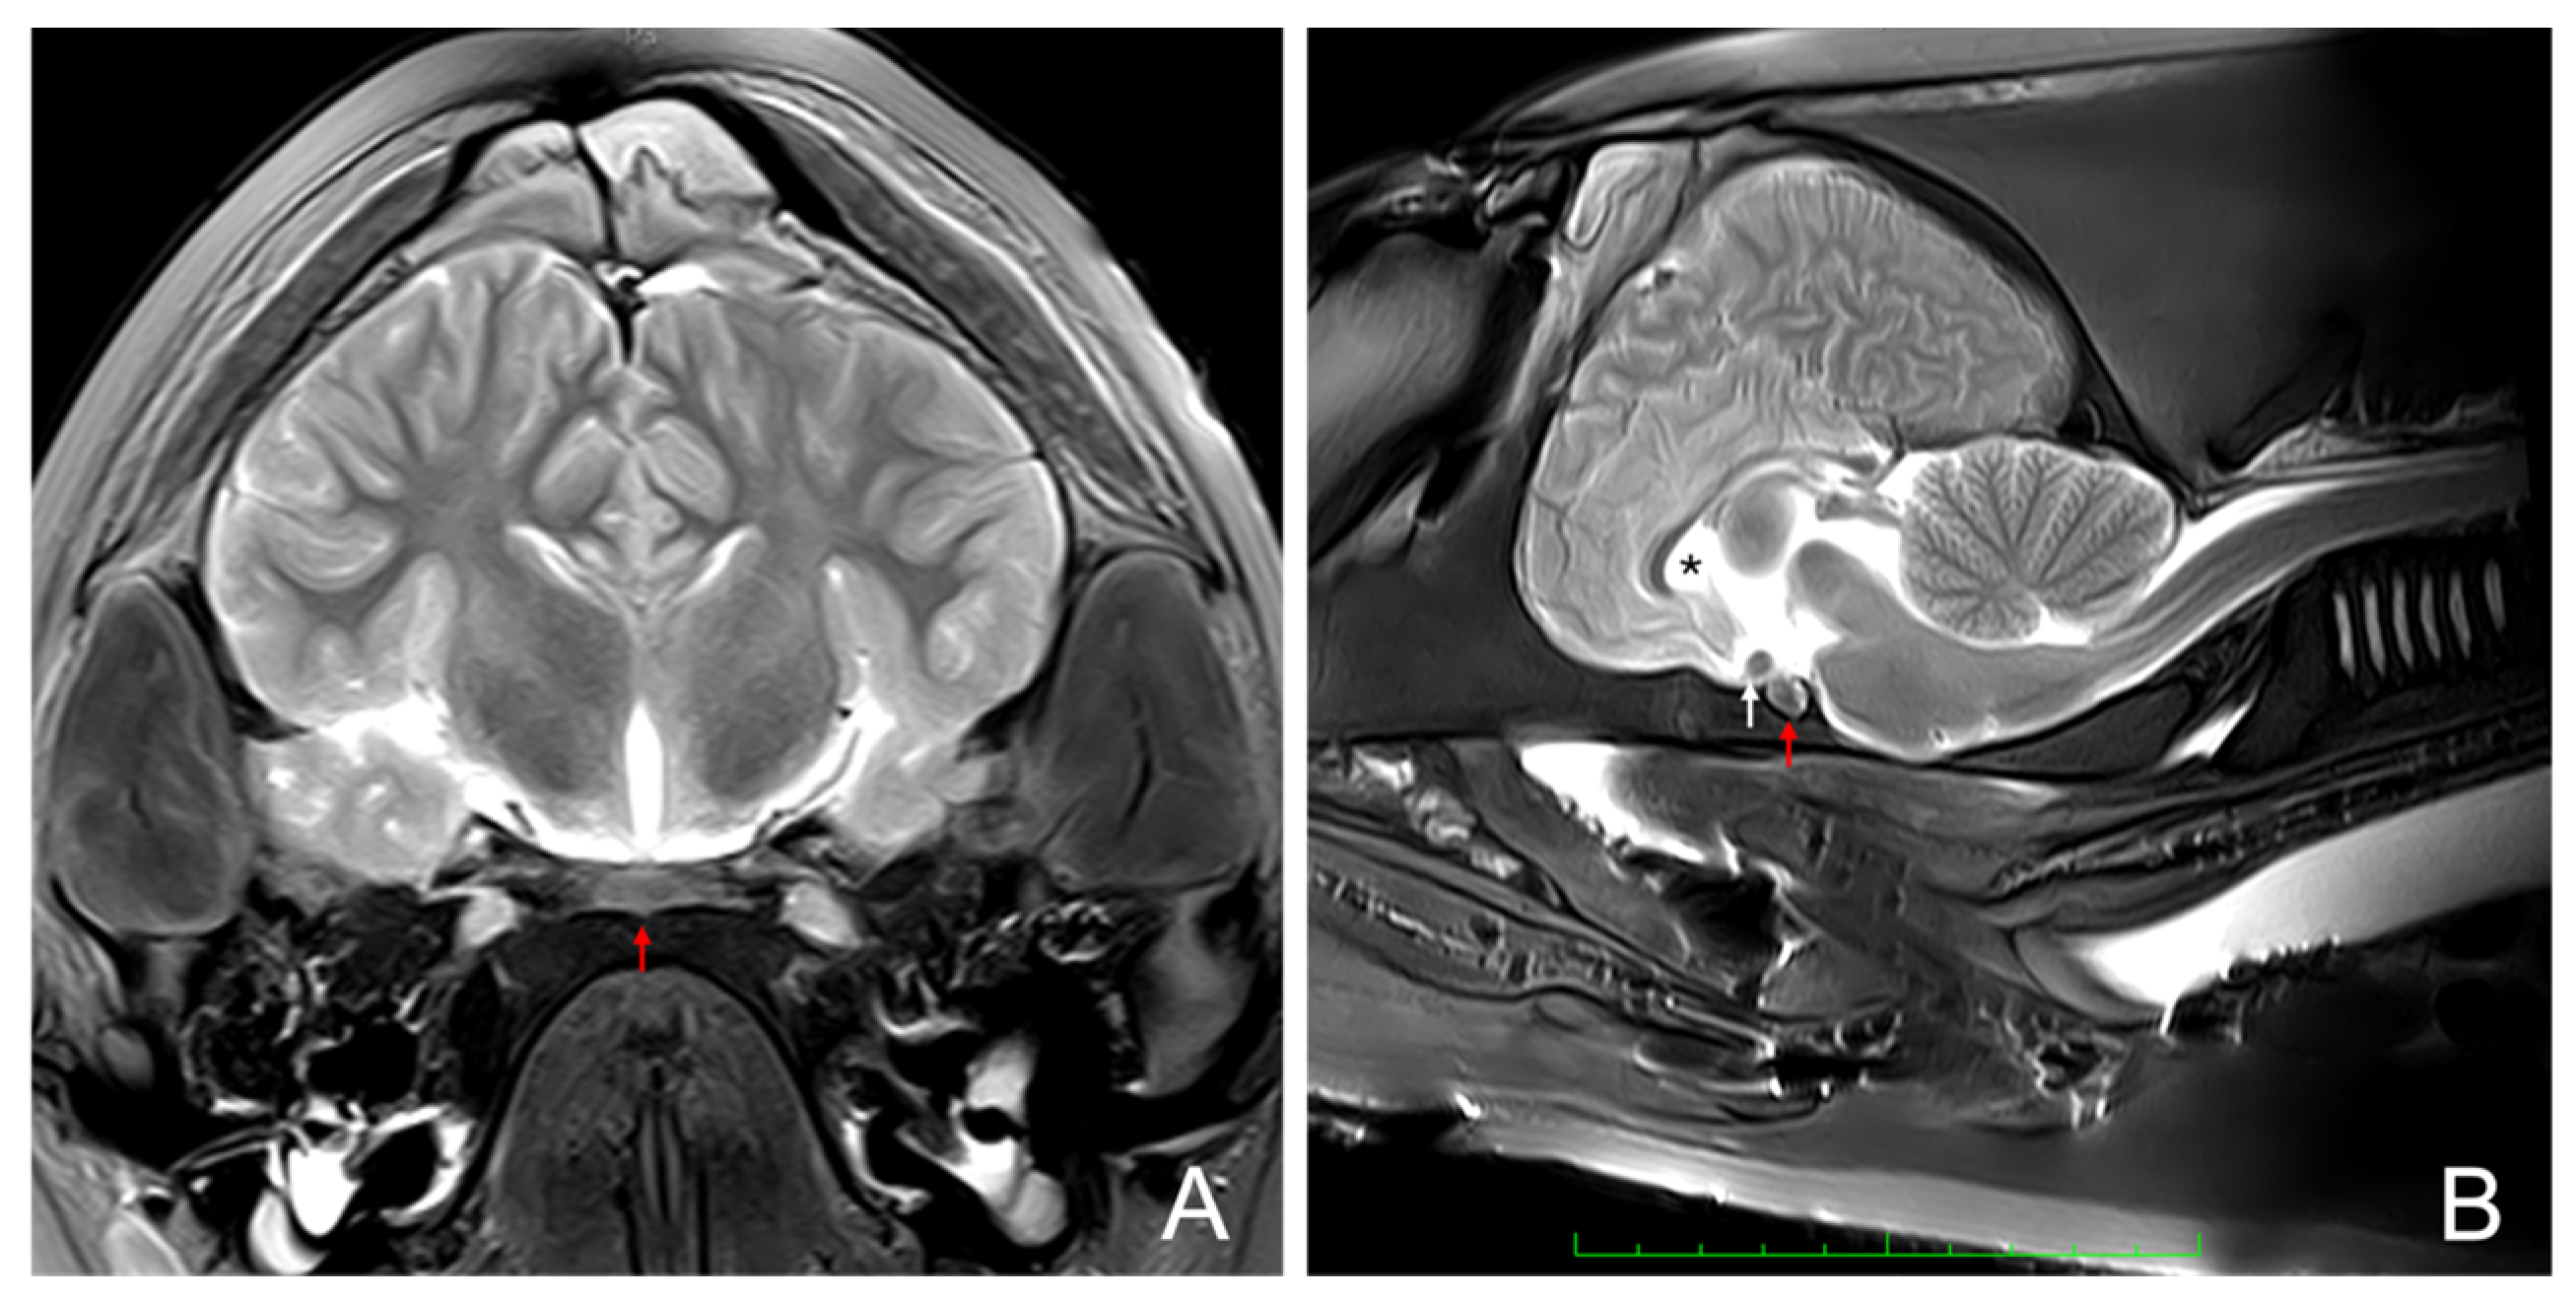

3.1. Magnetic Resonance Imaging

3.2. Gross Anatomical Description